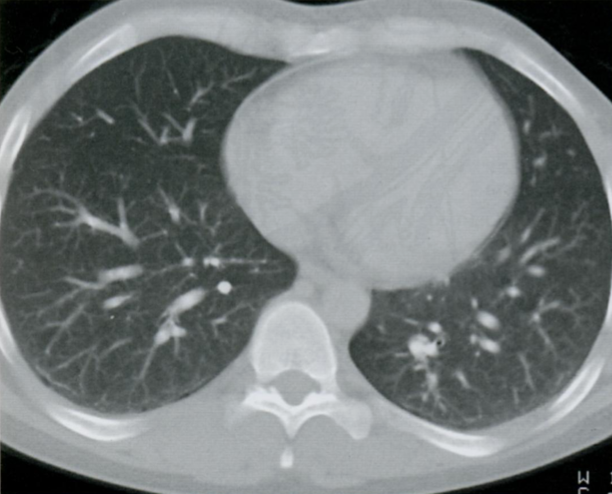

КТ грудной клетки №4

Назовите все анатомические структуры, которые Вы знаете, на данном КТ срезе (11).

Найдите грудные позвонки и грудину. Затем верхнюю полую вену, ушко правого предсердия, восходящую и нисходящую аорту, легочный ствол, левое предсердие и легочные сосуды, непарную вену и пищевод.

A

26 - грудные позвонки

24 - грудина

1 - верхняя полая вена

2а - ушко правого предсердия

7 - восходящая аорта

9 - легочный ствол

3 - левое предсердие

10 - сосуды легких

8 - нисходящая аорта

15 - непарная вена

16 - пищевод

Синим цветом отмечены номера сегментов.